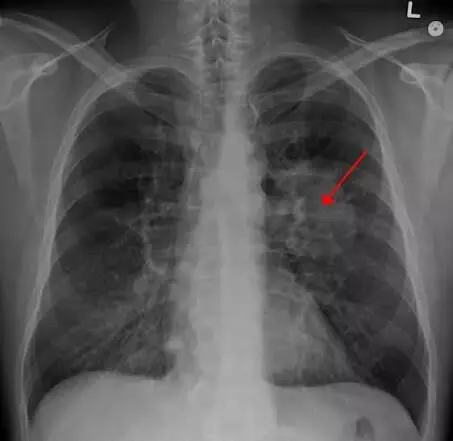

Lung Cancer : ప్రతి సంవత్సరం నవంబర్ నెలని ఊపిరితిత్తుల క్యాన్సర్ అవగాహన మాసంగా జరుపుకుంటారు. ఈ సందర్భంగా ఆరోగ్య నిపుణులు ఒక ముఖ్యమైన మరియు ఆందోళనకరమైన విషయాన్ని వెల్లడించారు: ధూమపానం (Smoking) చేయని వారిలో కూడా ఊపిరితిత్తుల క్యాన్సర్ (Lung Cancer) కేసులు గణనీయంగా పెరుగుతున్నాయి.

ధూమపానం చేయని యువకులు మరియు మధ్య వయస్కులలో కూడా ఈ కేసులు పెరగడం వైద్య నిపుణులను కలవరపెడుతోంది. క్యాన్సర్ను ప్రారంభ దశలోనే గుర్తించడానికి ముందుగా స్క్రీనింగ్ (Early Screening) చేయించుకోవడం చాలా ముఖ్యమని నిపుణులు ఉద్ఘాటిస్తున్నారు.

ఎవరికి స్క్రీనింగ్ అవసరం: ధూమపానం చేయకపోయినా, తరచుగా తీవ్రమైన వాయు కాలుష్యం ఉన్న ప్రాంతాల్లో నివసించేవారు లేదా కుటుంబంలో క్యాన్సర్ చరిత్ర ఉన్నవారు వైద్యుడిని సంప్రదించి, లో-డోస్ సీటీ స్కాన్ (Low-Dose CT Scan) వంటి స్క్రీనింగ్ పద్ధతులు తెలుసుకోవాలి.